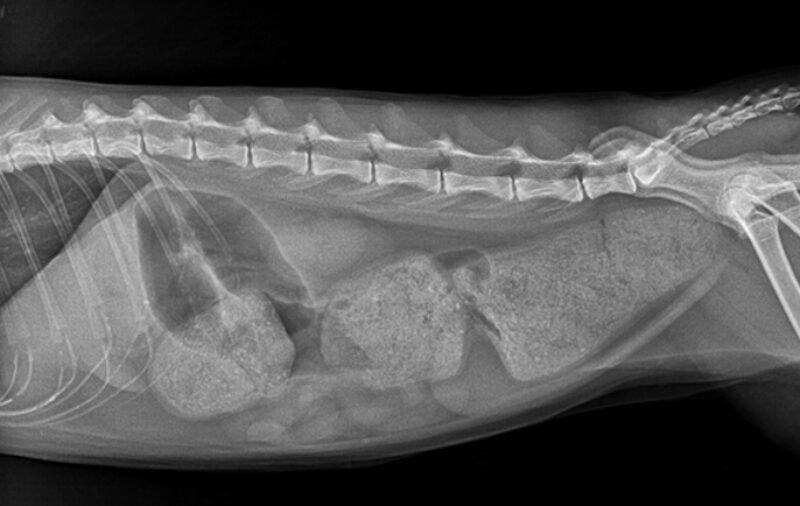

Eine zentrale Rolle spielt die bildgebende Diagnostik. Das Abdomenröntgen sollte immer in zwei Ebenen durchgeführt werden, um Beckenengstände oder alte Traumata sicher beurteilen zu können. Zur Diagnostik eines Megakolons wird der Kolondurchmesser mit der Länge des Wirbelkörpers von L7 verglichen. Ein Durchmesser von mehr als dem 1,5-fachen der L7-Länge gilt als zuverlässiger Hinweis auf ein Megakolon. Ultraschall kann strukturelle Veränderungen wie Entzündungen oder Neoplasien darstellen. Eine Kolonoskopie ist selten erforderlich, kann aber bei Strikturen oder intraluminalen Massen hilfreich sein. Bei neurologischen Auffälligkeiten können weiterführende Untersuchungen wie CT oder MRT notwendig werden.